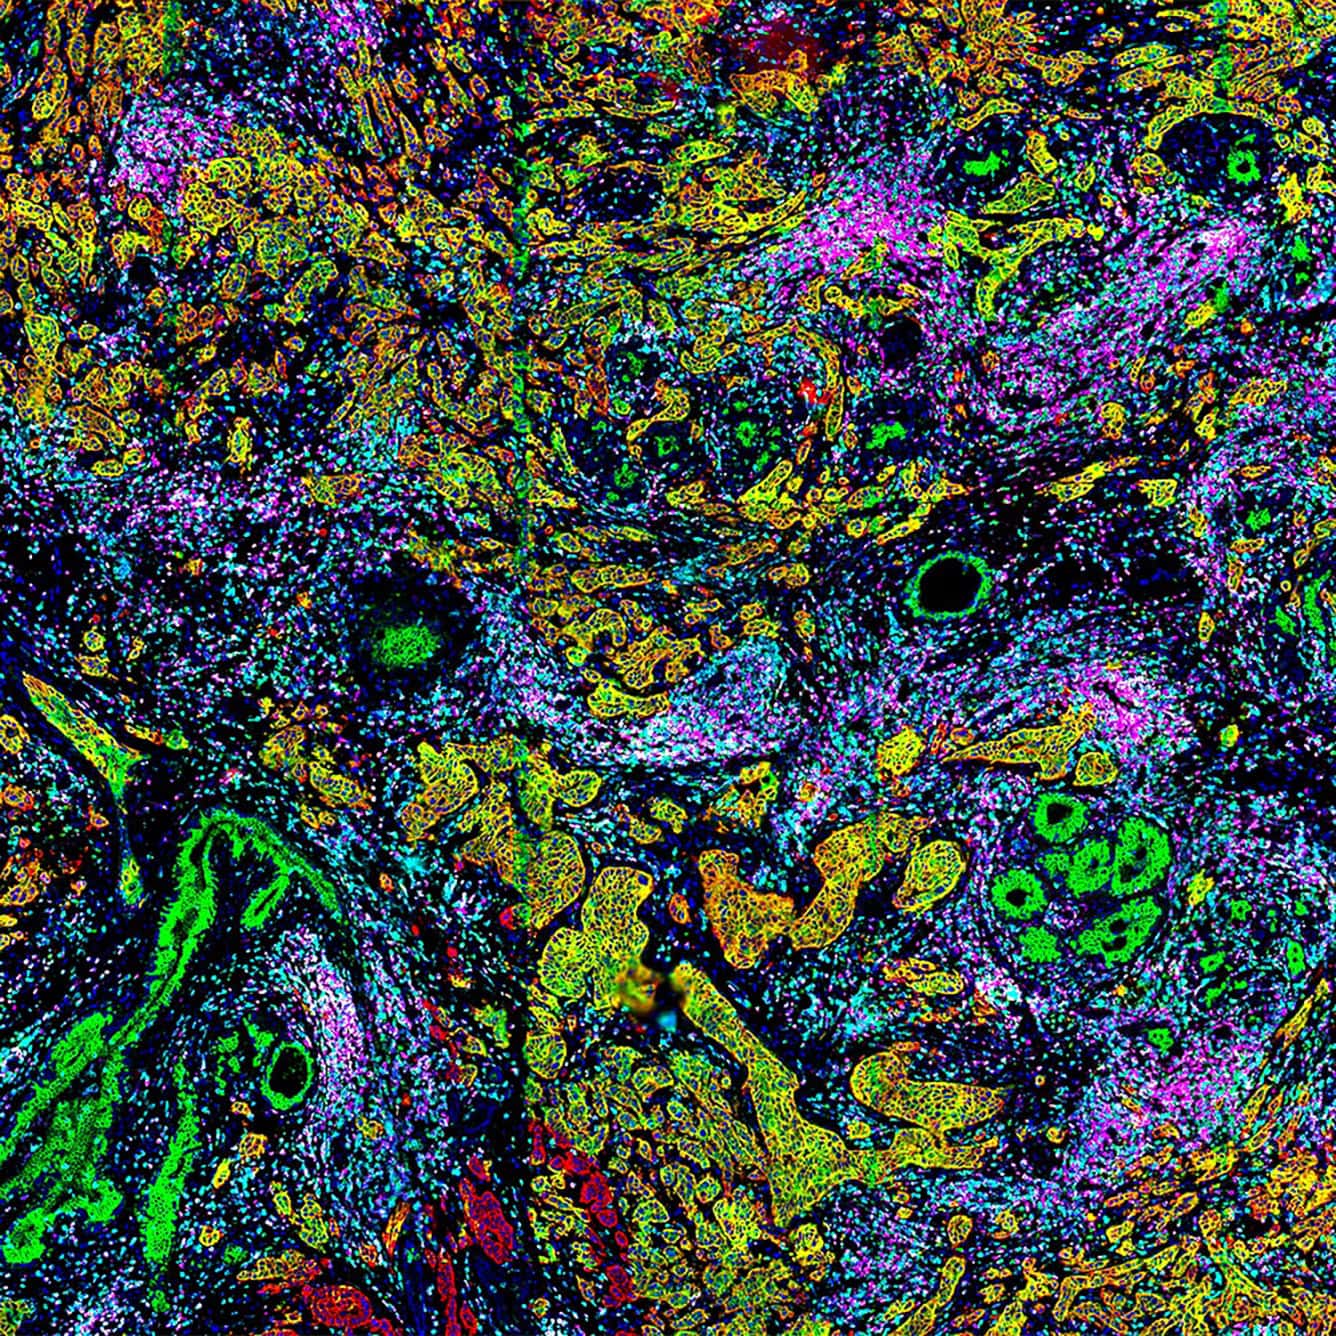

By combining 182 nm/pixel resolution, an 8-log dynamic range, and whole-slide imaging across more than 700 mm² of tissue, the CellScape XR platform enables confident identification of rare cell populations, accurate discrimination between low and high expressors, and precise phenotypic classification at single-cell and subcellular resolution.

High-resolution imaging for precise single-cell phenotyping across complex tissues

CellScape PSP delivers market-leading spatial proteomics, capturing the widest dynamic range of protein expression per cell while maintaining single-cell resolution across complex tissues. This high-resolution, high- dynamic-range imaging ensures accurate detection of low-, mid-, and high-expressing biomarkers, enabling confident single-cell phenotyping and robust quantitative insights

FFPE Breast Cancer

HDR Composite